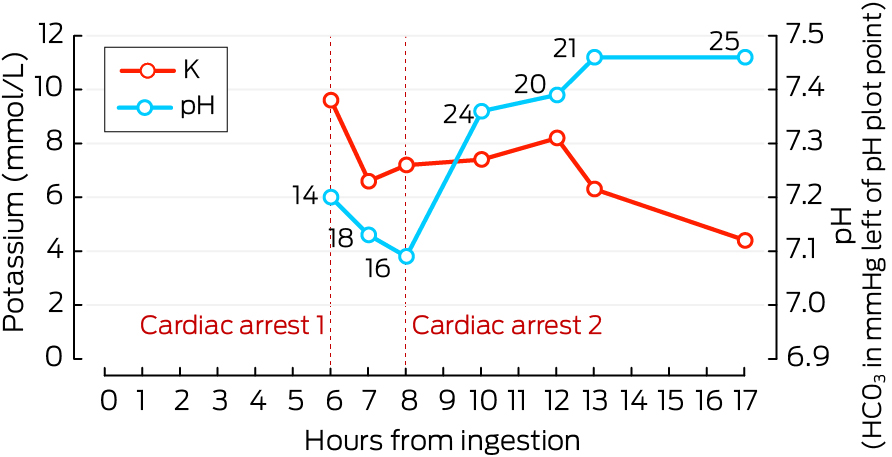

Initial venous blood gas (VBG) testing showed a potassium concentration of 9.6 mmol/L (reference interval: 3.4–4.8 mmol/L). Advice was sought from the Victorian Poisons Information Centre.

This led to a reduction of potassium levels to 6.6 mmol/L.

Two hours later and on arrival to the intensive care unit, a second cardiac arrest occurred due to recurrence of hyperkalaemia (potassium concentration of 7.2 mmol/L). CPR was performed for 11 minutes, including two defibrillator shocks of 200 J, resulting in RoSC (Box 3). Further treatment was given:

Despite the above treatment, the patient had persistent hyperkalaemia (potassium concentration of 7.2 mmol/L), which was further treated with actrapid (10 units), sodium polystyrene sulfonate (30 g), and 18 hours of continuous veno‐venous haemodiafiltration. Within 4 hours of starting this third round of treatment, the patient started to recover, before achieving successful resolution. The patient was extubated with good recovery of original cognition and discharged after a period of rehabilitation. Trends of potassium concentration and pH are presented on Box 4.